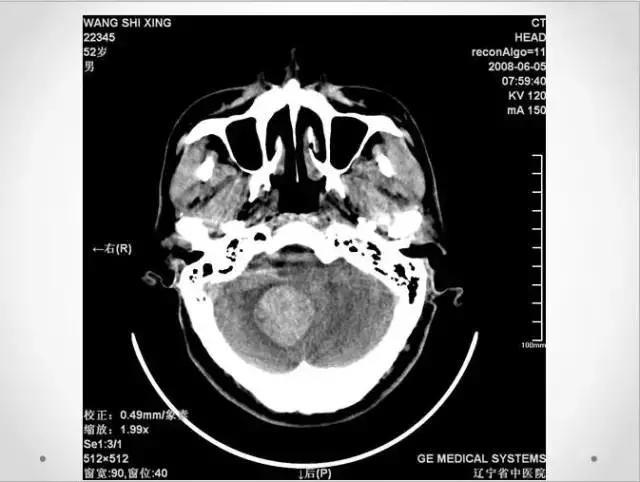

十分钟学会头部CT解剖(多图)

作为一准备毕业的实习生,收集了不少的资料,头颅CT一直是我比较头痛的,现将资料上传,与各位、特别是与我一样是实习生的同行们分享。